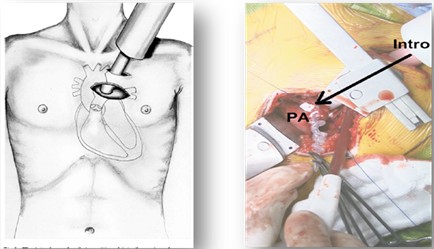

4. 小婴儿主动脉缩窄合并室间隔缺损

婴幼儿主动脉缩窄合并室间隔缺损比较常见,该类患儿较早出现严重肺充血和重度肺动脉高压, 往往表现为喂养困难, 低体重, 反复呼吸道感染和心衰,因而需尽早手术。目前大多医生采用正中切口,一次性外科手术解除主动脉缩窄和并修补室缺,但需要深低温停循环和局部脑灌注,手术时间长, 创伤大,术后恢复亦颇费周折。为提高此类患儿的疗效,阜外医院自2008年起采用Hybrid 技术一期经胸矫治小婴儿主动脉缩窄合并室间隔缺损,首次将球囊扩张术融入心脏外科手术中。与经皮球囊成形术相比,其操作明显简单, 有效避免了经外周血管径路受限及股动脉损伤等问题。与常规外科手术相比,可简化手术,免除深低温停循环或局部脑灌注, 明显缩短手术时间, 促进术后恢复。该项技术对于病情危重, 反复肺部感染, 严重营养不良的主动脉缩窄合并室间隔缺损的小婴儿, 不失为一种简单、安全、有效的可选择的方法。

图注:在一站式杂交手术室内同期进行主动脉狭窄球囊扩张术(左)及室间隔缺损修补术(右)